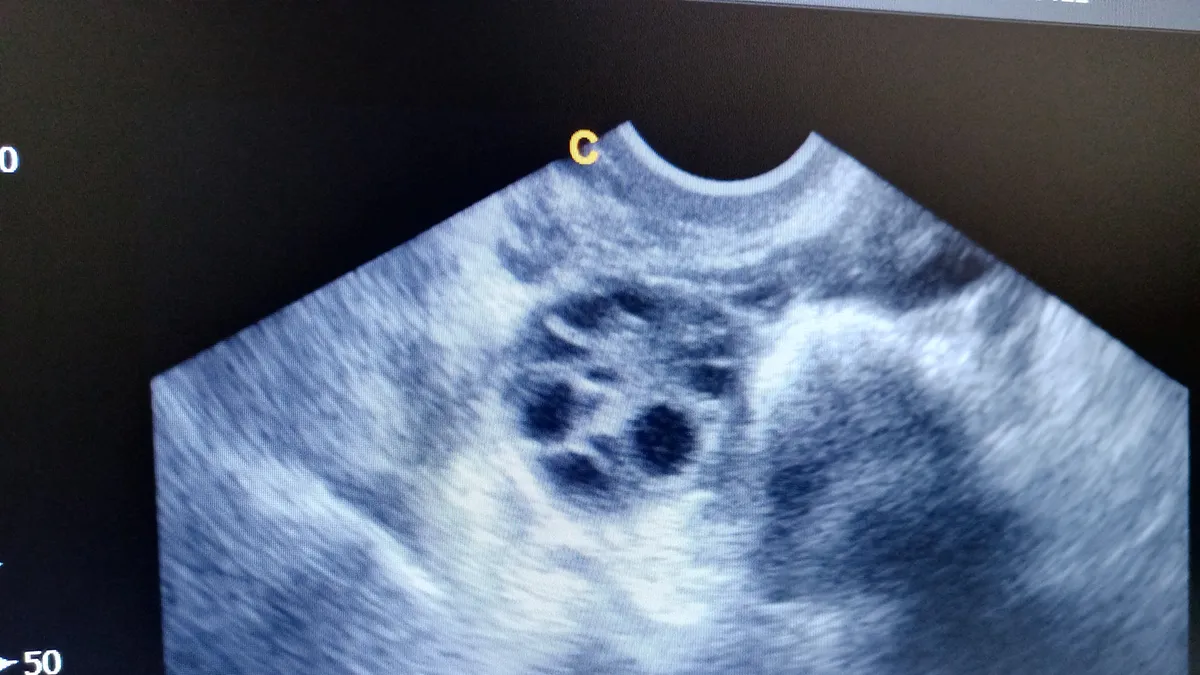

Polycystic ovaries on ultrasound

One or both ovaries become enlarged and collect many fluid-filled follicles, up to 8mm (approximately 0.3in) that surround the immature eggs, placed around the edge of the ovary - this is the "string of pearls" we spoke of at the beginning.

Then you'll get a physical exam, which will include looking for the physical signs of PCOS. Some of them we can see, like the dark velvety patches or skintags, excess hair, or hair thinning. For what we can’t see, you may get an ultrasound (over the belly for those who are not yet sexually active or transvaginal for those who are). The exam checks to see if your ovaries are enlarged or swollen and if you have the characteristic "pearls" on the edges. If doing an ultrasound, the doctor will also check the thickness of your endometrium (the lining of your uterus, or womb). It may be thickened if your period has been absent.